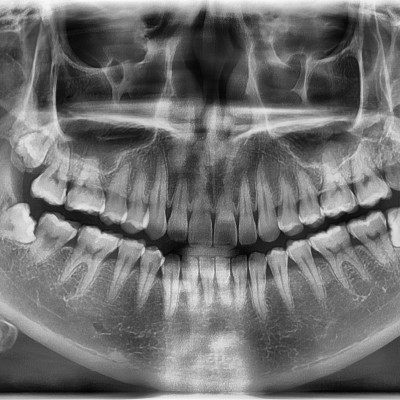

#18,28,38 48 사랑니 발치 #18,28,38,48 사랑니 발치 구강 외과 전문의가 당일 발치했습니다. ----------------------..

작성자 이턱이 작성일 02-04 조회 1